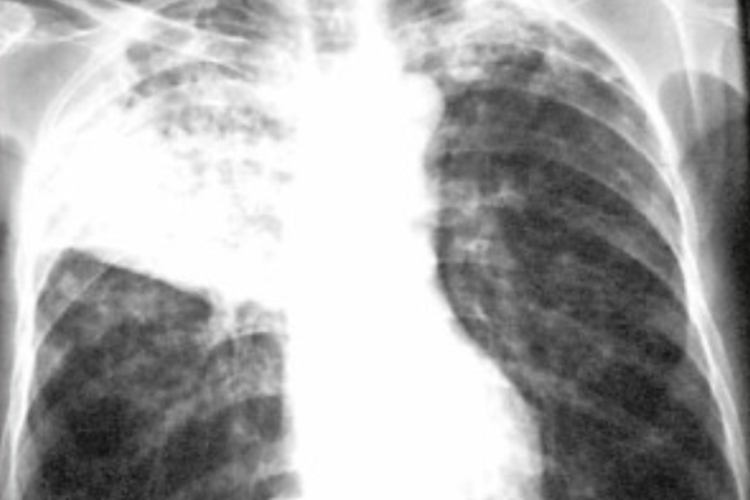

浸润型肺结核:表现为小片状或斑点状阴影,可融合和形成空洞。

干酪性肺炎:呈大叶性密度均匀磨玻璃状阴影,逐渐出现溶解区,呈虫蚀样空洞,可出现播散病灶。